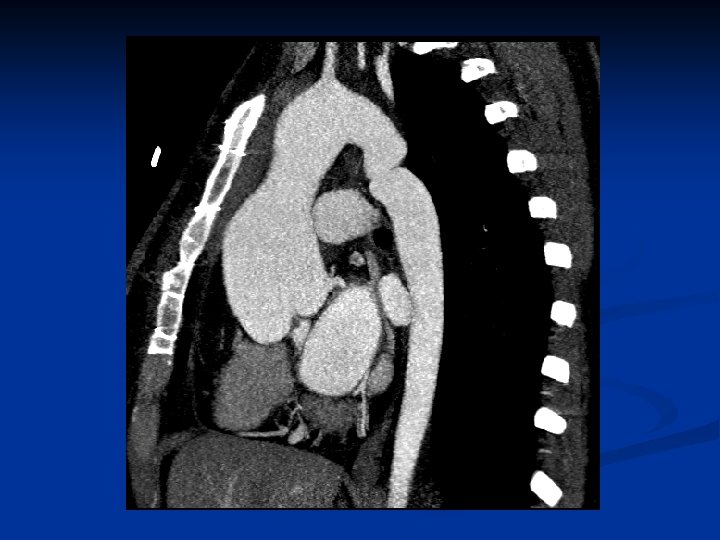

Cardiovascular n Major criteria: n Aortic-root dilatation: ( 70 -80%) n Aortic dissections involving the ascending aorta n Minor criteria: n Mitral valve prolapse (55 -69%) n Dilatation of proximal main pulmonary artery without pulmonic stenosis or other cause n Calcification of mitral annulus (patients <40 y) n Dilatation of abdominal or descending thoracic aorta (patients <50 y) n For the CV system to be involved, need 1 minor criterion

Echocardiography Diagnosis and management of aortic-root dilatation The upper limit of the normal aortic root size is 1. 9 cm/m 2 of body surface area n Assesses mitral-valve prolapse, LV size / function, LA size, and tricuspid valve function n TEE assesses the distal ascending and descending aorta and prosthetic valves n Doppler echocardiography - detecting and grading aortic and mitral regurgitation n

CT and MRI for assessing chronic dissection of the aorta - any patient who has an aortic-root dimension >150% of the mean for their body surface area or - ratio of actual to predicted aortic-root dimension >1. 5 n CT or MRI of the lumbosacral spine to evaluate for dural ectasia n

Treatment n Cardiovascular surgery CV surgery can substantially prolong survival Prophylactic / emergency CV surgery is needed for: - aortic and mitral regurgitation - aortic aneurysm - aortic dissection n In cases of acute proximal aortic dissection, emergency surgical replacement of the aortic root is performed n

Treatment The ascending aorta is usually replaced when the diameter exceeds 55 -60 mm n Composite valve-graft replacement is performed - prosthetic valve sewn into a tube graft with reimplantation of the coronary ostia (modified Bentall procedure) n Low rates of morbidity and mortality n